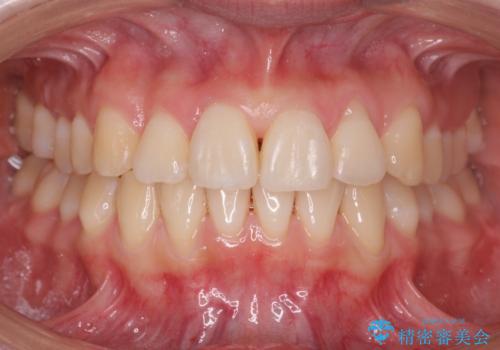

上の奥歯を後ろに下げて前歯のねじれを治すスペースを確保しました。

奥歯を後ろに下げるために、矯正用インプラントを使用しています。